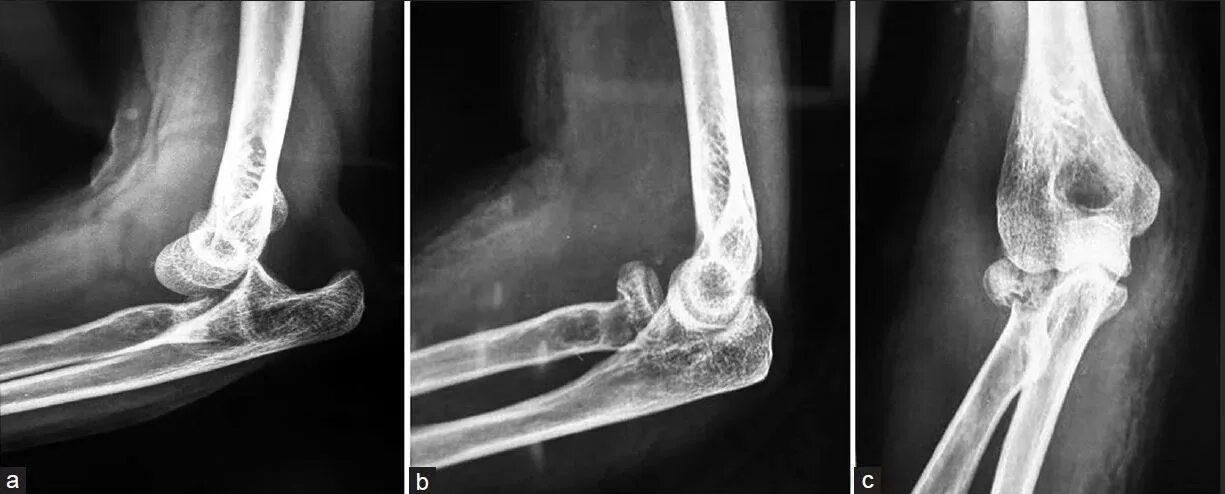

Перелом локтевой сустав мкб 10